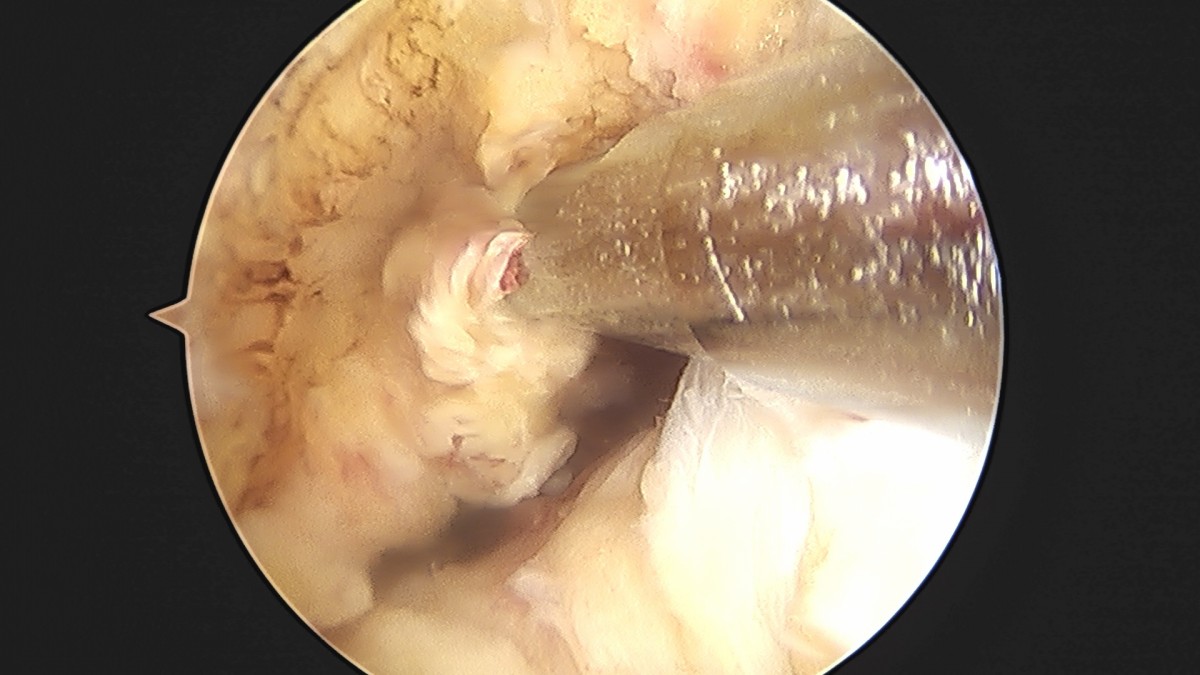

이재상원장님 전방십자인대 재건술 및 반월상 연골판 봉합술 윤두O 환자

dae765e4d9ac96aee867c9d6292d8784_1758007347_2498.jpg